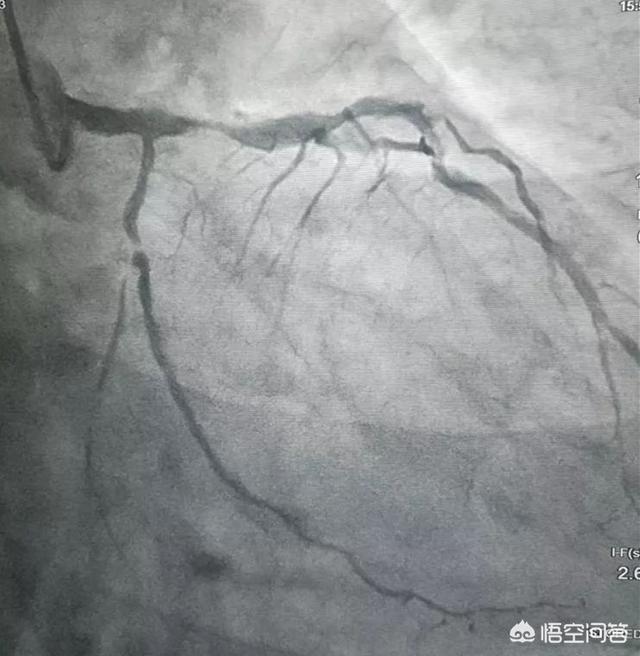

Ein Herzstent, auch als Koronarstent bezeichnet, ist ein Gerät, das bei der PTCA (perkutane transluminale Koronarangioplastie) eingesetzt wird. Herzstents sehen aus wie winzige Metallröhrchen mit Netzwand außerhalb des Körpers und bestehen aus Drähten und Mikrokapseln an der Vorderseite der Drähte usw. Kleine Stents wiegen sogar weniger als ein Zehntausendstel Gramm. Arterielle Stents können kontinuierlich dazu beitragen, Arterien zu stützen, Verengungen zu beheben und einen reibungslosen Blutfluss zu gewährleisten. Sie werden in der Regel bei der Behandlung des akuten Myokardinfarkts und anderer akuter Koronarsyndrome eingesetzt, um das Leben des Patienten zu retten oder seine Lebensqualität zu verbessern.

Cardiac Stent Chirurgie ist zunächst von einer Person Arm oder Bein Arterie zu öffnen, eine kleine Öffnung, die mit der Leitung eine Sonde, die mit einem genau wie eine kleine Kugel geladen ist, durch Ultraschall-Beobachtung der kleinen Kugel, um die Koronararterie Blutgefäße in der Lage der Blockade nach der Kugel, um die Kugel, die ein Regenschirm aus Eisen, ganz plötzlich die Blutgefäße zur Unterstützung der Blutgefäße, so dass die Blutgefäße sind vorübergehend gestützt, so dass das Blut kommen kann.